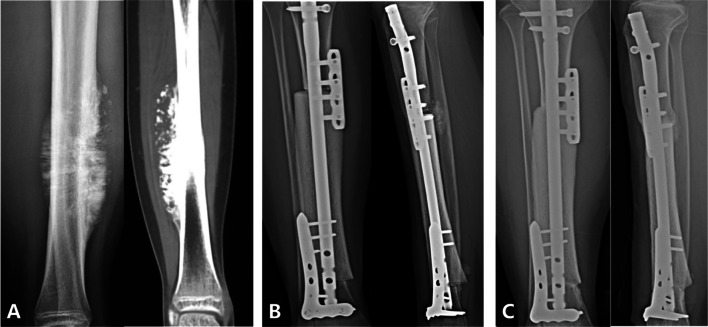

Methods: A retrospective study was conducted on 144 patients who underwent intercalary biological reconstruction for primary malignant bone tumors at a single institution between January 2012 and July 2023. Seventy-two patients underwent intercalary liquid nitrogen-frozen autograft reconstruction, and 72 patients underwent intercalary allograft reconstruction in this study. A modified International Society of Limb Salvage classification system was used to evaluate the complications.

Results: The mean follow-up time was 60.2 ± 32.1 (range, 12-149) months. The mean union time was 9.6 months in the frozen autograft group and 15.9 months in the allograft group (p < 0.001). The 5-year overall survivorship was 86.8% in the frozen autograft group and 73.2% in the allograft group (p = 0.017). The average MSTS-93 score was comparable between the two groups (89.7% by autograft versus 87.6% by allograft, p > 0.05). Of the patients, 48.6% (70/144) had at least one complication. The most common complications were bone nonunion (20.8%, 30/144), followed by structural failure (17.4%, 25/144), tumor progression (10.4%, 15/144), infection (10.4%, 15/144), and soft tissue failures (5.6%, 8/144). Higher rates of bone nonunion (type 4B; p = 0.002) and structural failure (type 3B; p = 0.004) were obtained in the allograft group than in the frozen autograft group.

Conclusions: The intercalary frozen autografts had shorter union time and lower complication rates than allograft reconstruction. Therefore, we recommend that frozen autograft reconstruction be considered when the tumor bone has not suffered severe osteolytic injury or pathological fracture.